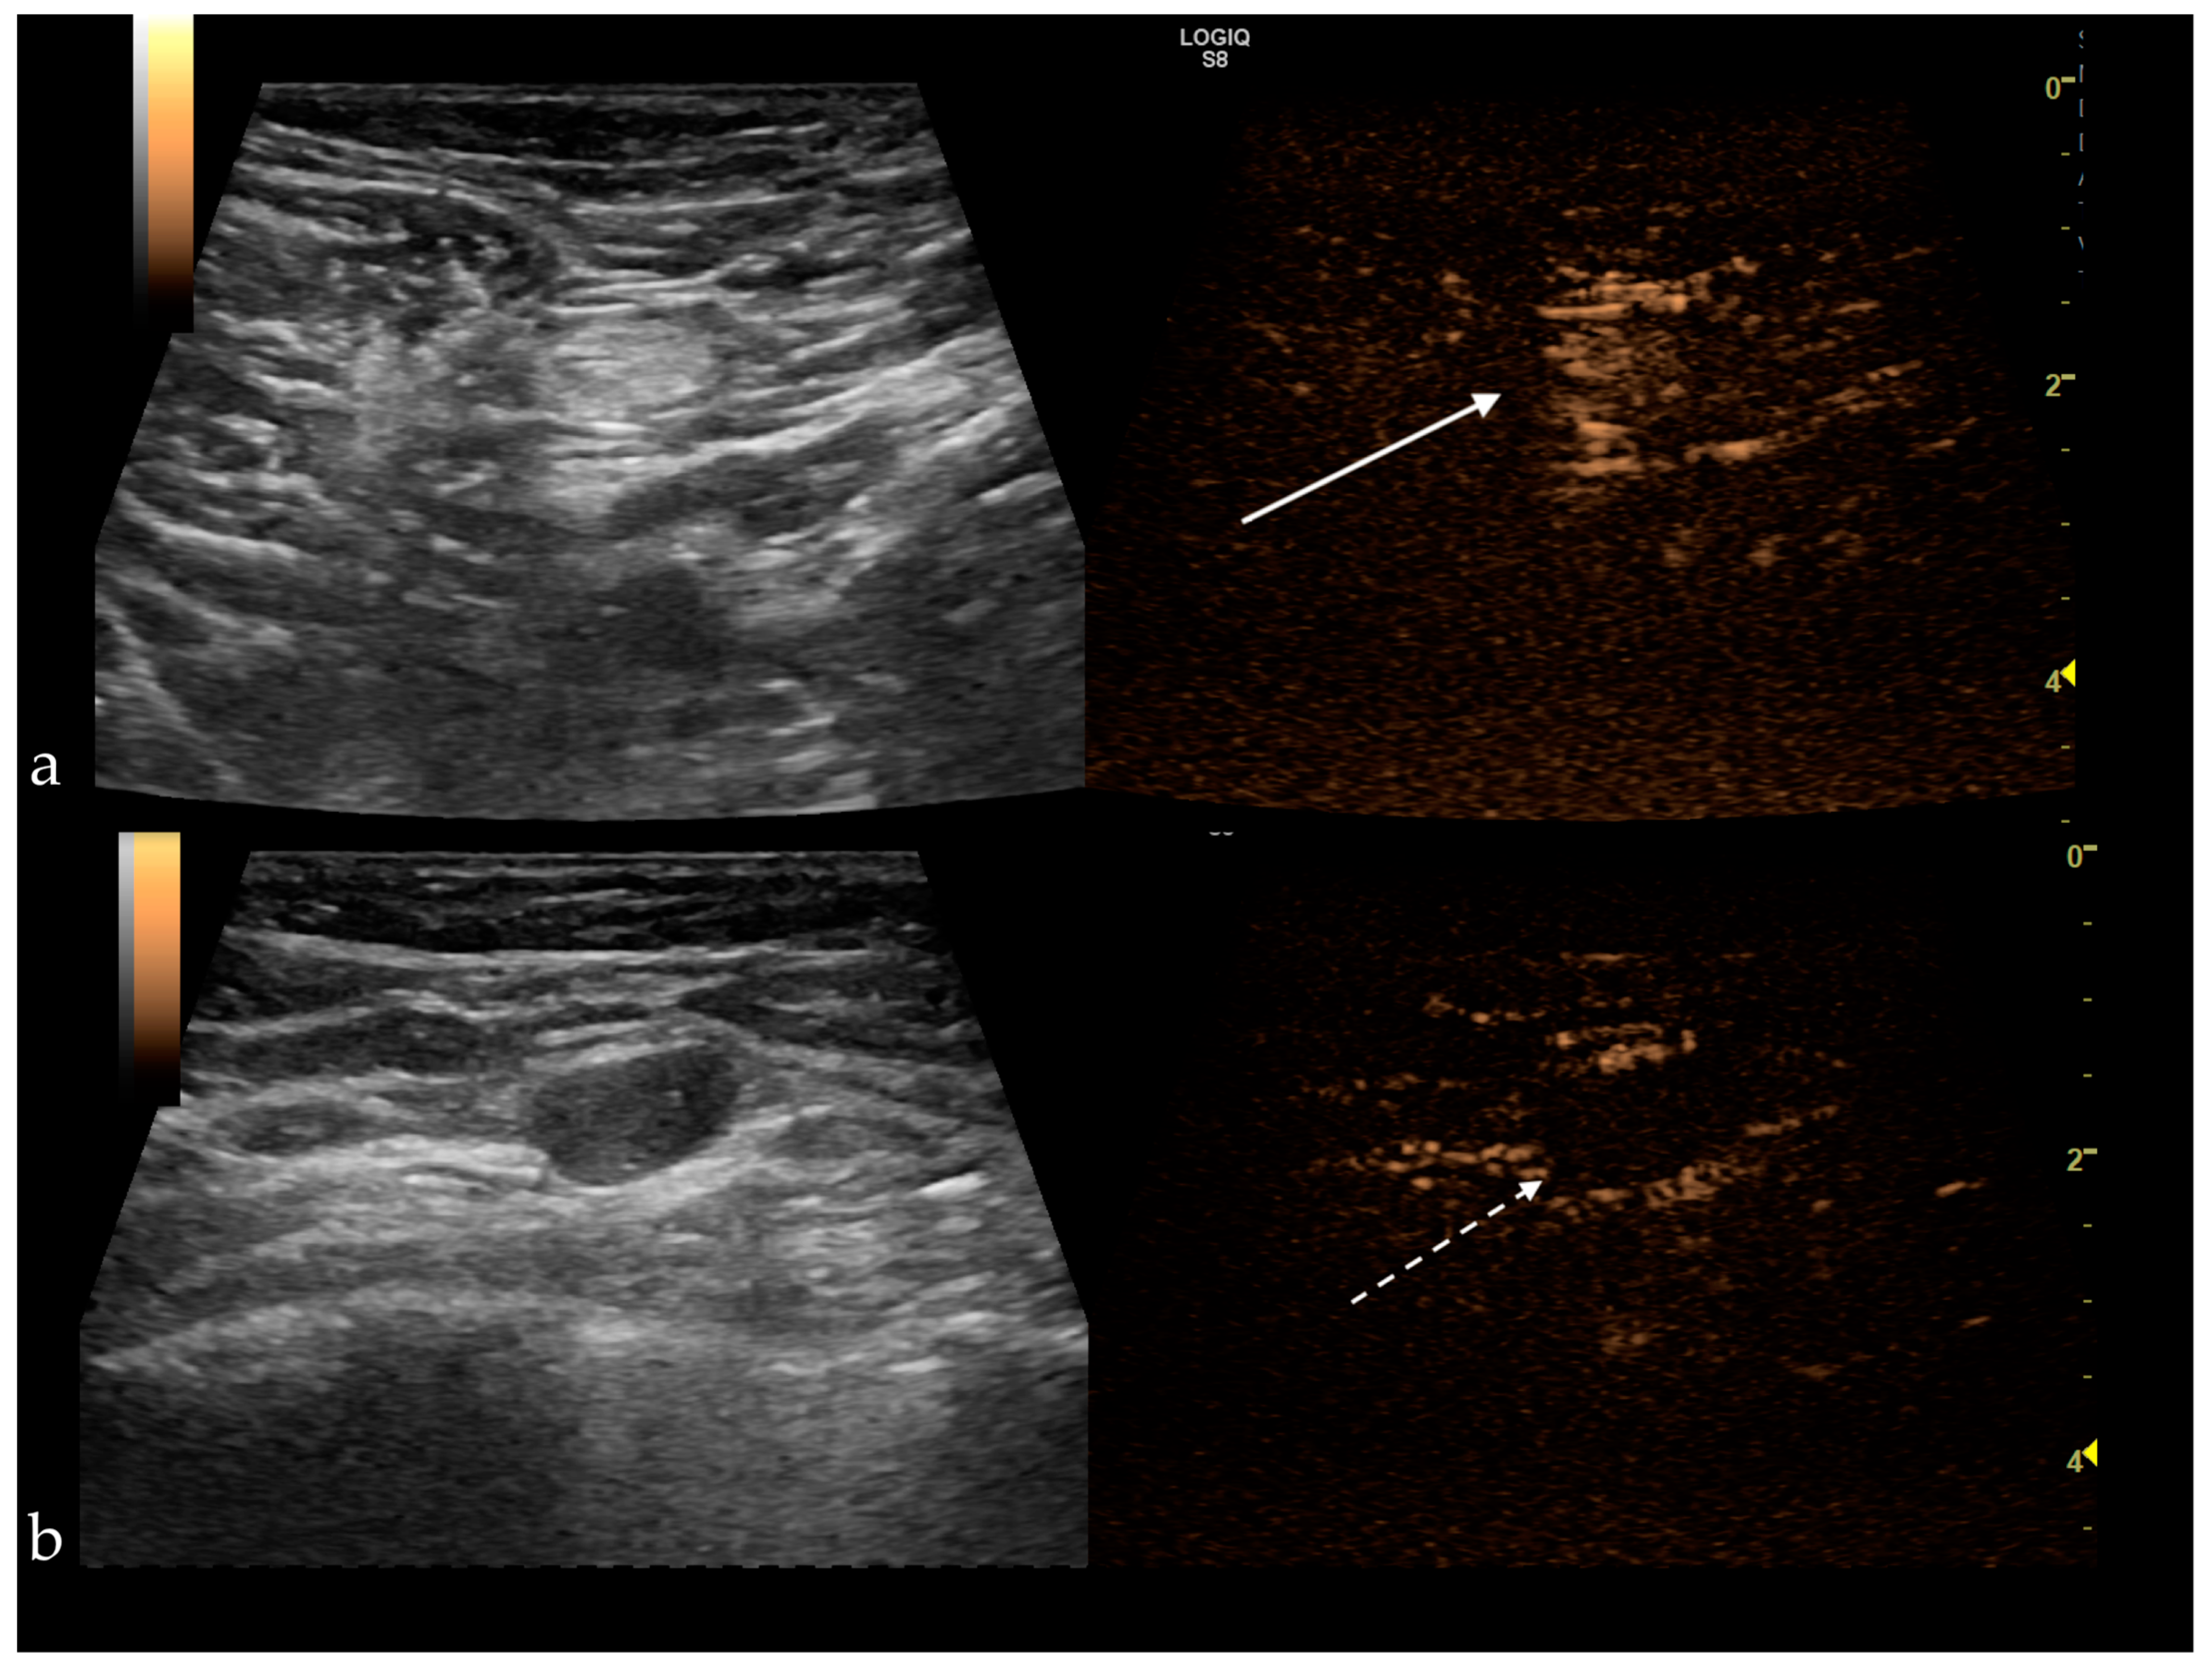

Figure 4. (a) Benign sentinel lymph node presenting a homogenous central enhancement (white arrow); (b) Metastatic sentinel lymph node with no enhancement after subcutaneous administration of the contrast agent (white dotted arrow).

SLNs enhancing patterns may be useful in making the differential diagnosis. Zhao et al. and Xie et al. described three types of enhancement:

• type I—homogeneous enhancement.

• type II—heterogeneous uptake (regional or diffuse), with hypoperfusion or unperfused areas.

• type III—poor or no enhancement [50,51].

Type I was considered benign, types II and III were deemed malignant (Figure 4), yielding a sensitivity (Se) of 100%, a specificity (Sp) of 52%, with a positive predictive value of 64.9%, negative predictive value of 100% and a diagnostic accuracy of 64.9%. Therefore, the homogeneous enhancement has the highest negative predictive value, representing an indicator of benignity. In contrast, inhomogeneous or no enhancement is due to perfusion defects and is significantly associated with lymph node tumor infiltration [50,52]. The sentinel node’s heterogeneous appearance was observed in the case of Her2 positive tumors and in tumors ≥2 cm [9,29,33].